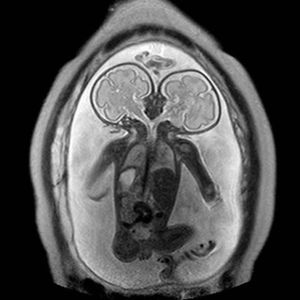

MRI showing a fetus with two separate heads, a common thorax, abdomen and pelvis with a single pair of upper and lower limbs!There are nearly a dozen different types of conjoined twins. One of the most common classifications is thoracopagus twins. These twins are connected at the upper portion of the torso.Thoracopagus twins share a heart, which, depending on how closely they are joined, makes it nearly impossible to separate them and save them both. That type make up about 40% of all conjoined cases.Another common type of conjunction is called omphalopagus, where twins are connected from the breastbone to the waist. About 33% of all conjoined cases are categorized as omphalopagus. These twins may share a liver, gastrointestinal or genitourinary functions, but rarely share a heart.One of the rarest types of conjoined twins is craniophagus twins, which are joined at the cranium or head. In fact, only 2% of all conjoined twins are joined in this way.